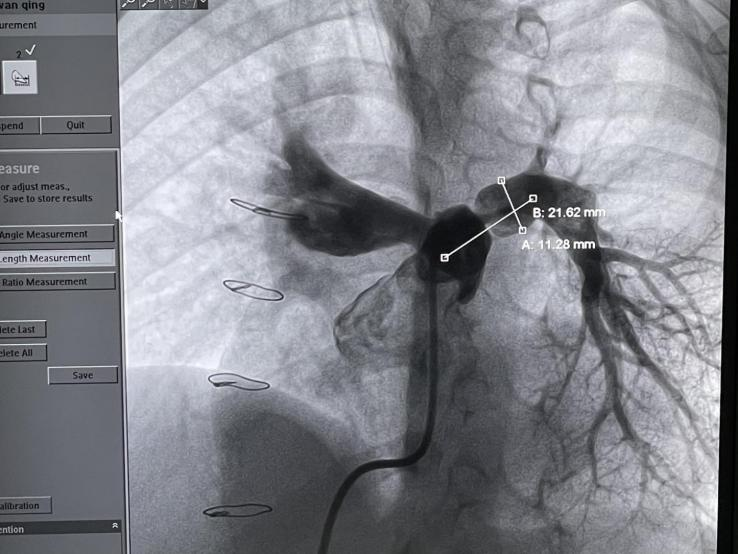

术中造影确认肺动脉狭窄长单21.62mm,狭窄处毗邻血管直径为11.28mm,根据患者情况,选择PAS.S30肺动脉支架。